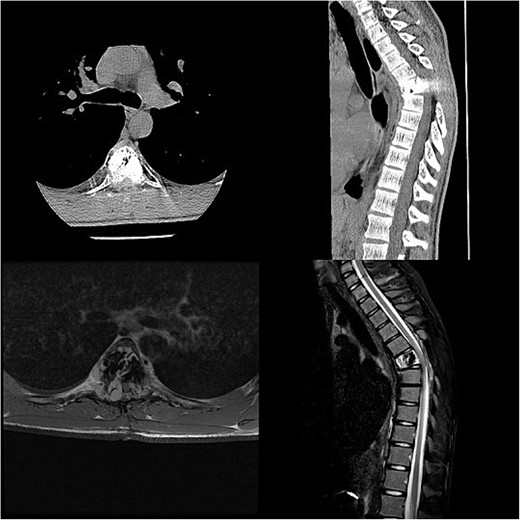

Three and a half years prior to admission to our institution, the patient underwent emergent Th6 vertebroplasty with laminectomy for a radiologically characteristic and histologically confirmed Th6 AVH causing acute thoracic myelopathy with a week-long paresis of the right foot dorsiflexion, performed by another surgeon. A progressive kyphotic deformity of the Th6 vertebrae was observed on radiographic follow-ups, whereby the hypoesthesia on the right anterior thigh persisted (ASIA score D, VAS pain score 7). Follow-up MRI and CT imaging revealed recurrent AVH of the Th6 vertebrae expanding into the spinal canal, leading to newly recognized worsening of myelopathy (Fig. 1). Additionally, a concomitant haemangioma was observed in the right transverse and articular process of Th8 (Fig. 2).

Follow-up CT imaging revealed recurrent AVH of the Th6 vertebrae, MRI scan showing AVH expanding into the spinal canal and causing myelopathy.